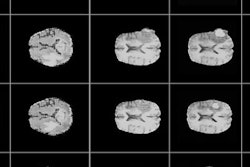

First image: Standard, high-dose CT at 12.4 mGy. Second image: Ultralow-dose CT at 1.3 mGy. Third image: AI-enhanced ultralow-dose CT at 1.3 mGy. Diagnostic image quality between the first and third images were rated as comparable by independent radiologists, despite a significant dose reduction of 11.1 mGy. The second image is noisy and nondiagnostic.